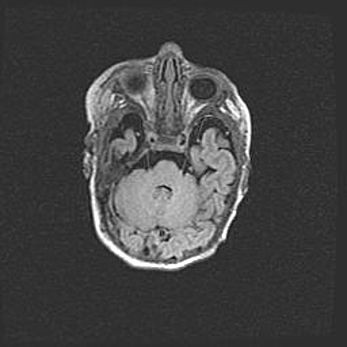

Множественные кисты обоих полушарий головного мозга, наибольшая из них в правой затылочной области. Ассиметричная атрофическая гидроцефалия.

Возраст: 7 месяцев

Вес: 5660 г

Пол: мужской

Окружность головы: 41,5 см

Срок гестации: 28-29 недель

Кисты головного мозга развиваются в результате многоочаговых некрозов вещества мозга и возникают вследствие перенесенной перинатальной инфекции, менингитов, энцефалитов, асфиксии, родовой травмы, расстройств мозгового кровообращения различного генеза. Образованию кист в веществе головного мозга плодов и новорожденных способствуют такие факторы, как высокое содержание в нем воды, недостаточная (или отсутствие) миелинизация и слабая астроглиальная реакция на повреждение.

Кисты могут сочетаться с гидроцефалией и другими поражениями головного мозга.